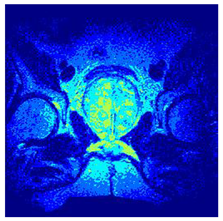

| Image | nt = 3 | nt = 4 | nt = 5 | nt = 8 |

|---|---|---|---|---|

| 1 | ![]() | ![]() | ![]() | ![]() |

| 2 | ![]() | ![]() | ![]() | ![]() |

| 3 | ![]() | ![]() | ![]() | ![]() |

| 4 | ![]() | ![]() | ![]() | ![]() |

| 5 | ![]() | ![]() | ![]() | ![]() |

| 6 | ![]() | ![]() | ![]() | ![]() |

| 7 | ![]() | ![]() | ![]() | ![]() |

| 8 | ![]() | ![]() | ![]() | ![]() |

| 9 | ![]() | ![]() | ![]() | ![]() |

| 10 | ![]() | ![]() | ![]() | ![]() |

| 11 | ![]() | ![]() | ![]() | ![]() |